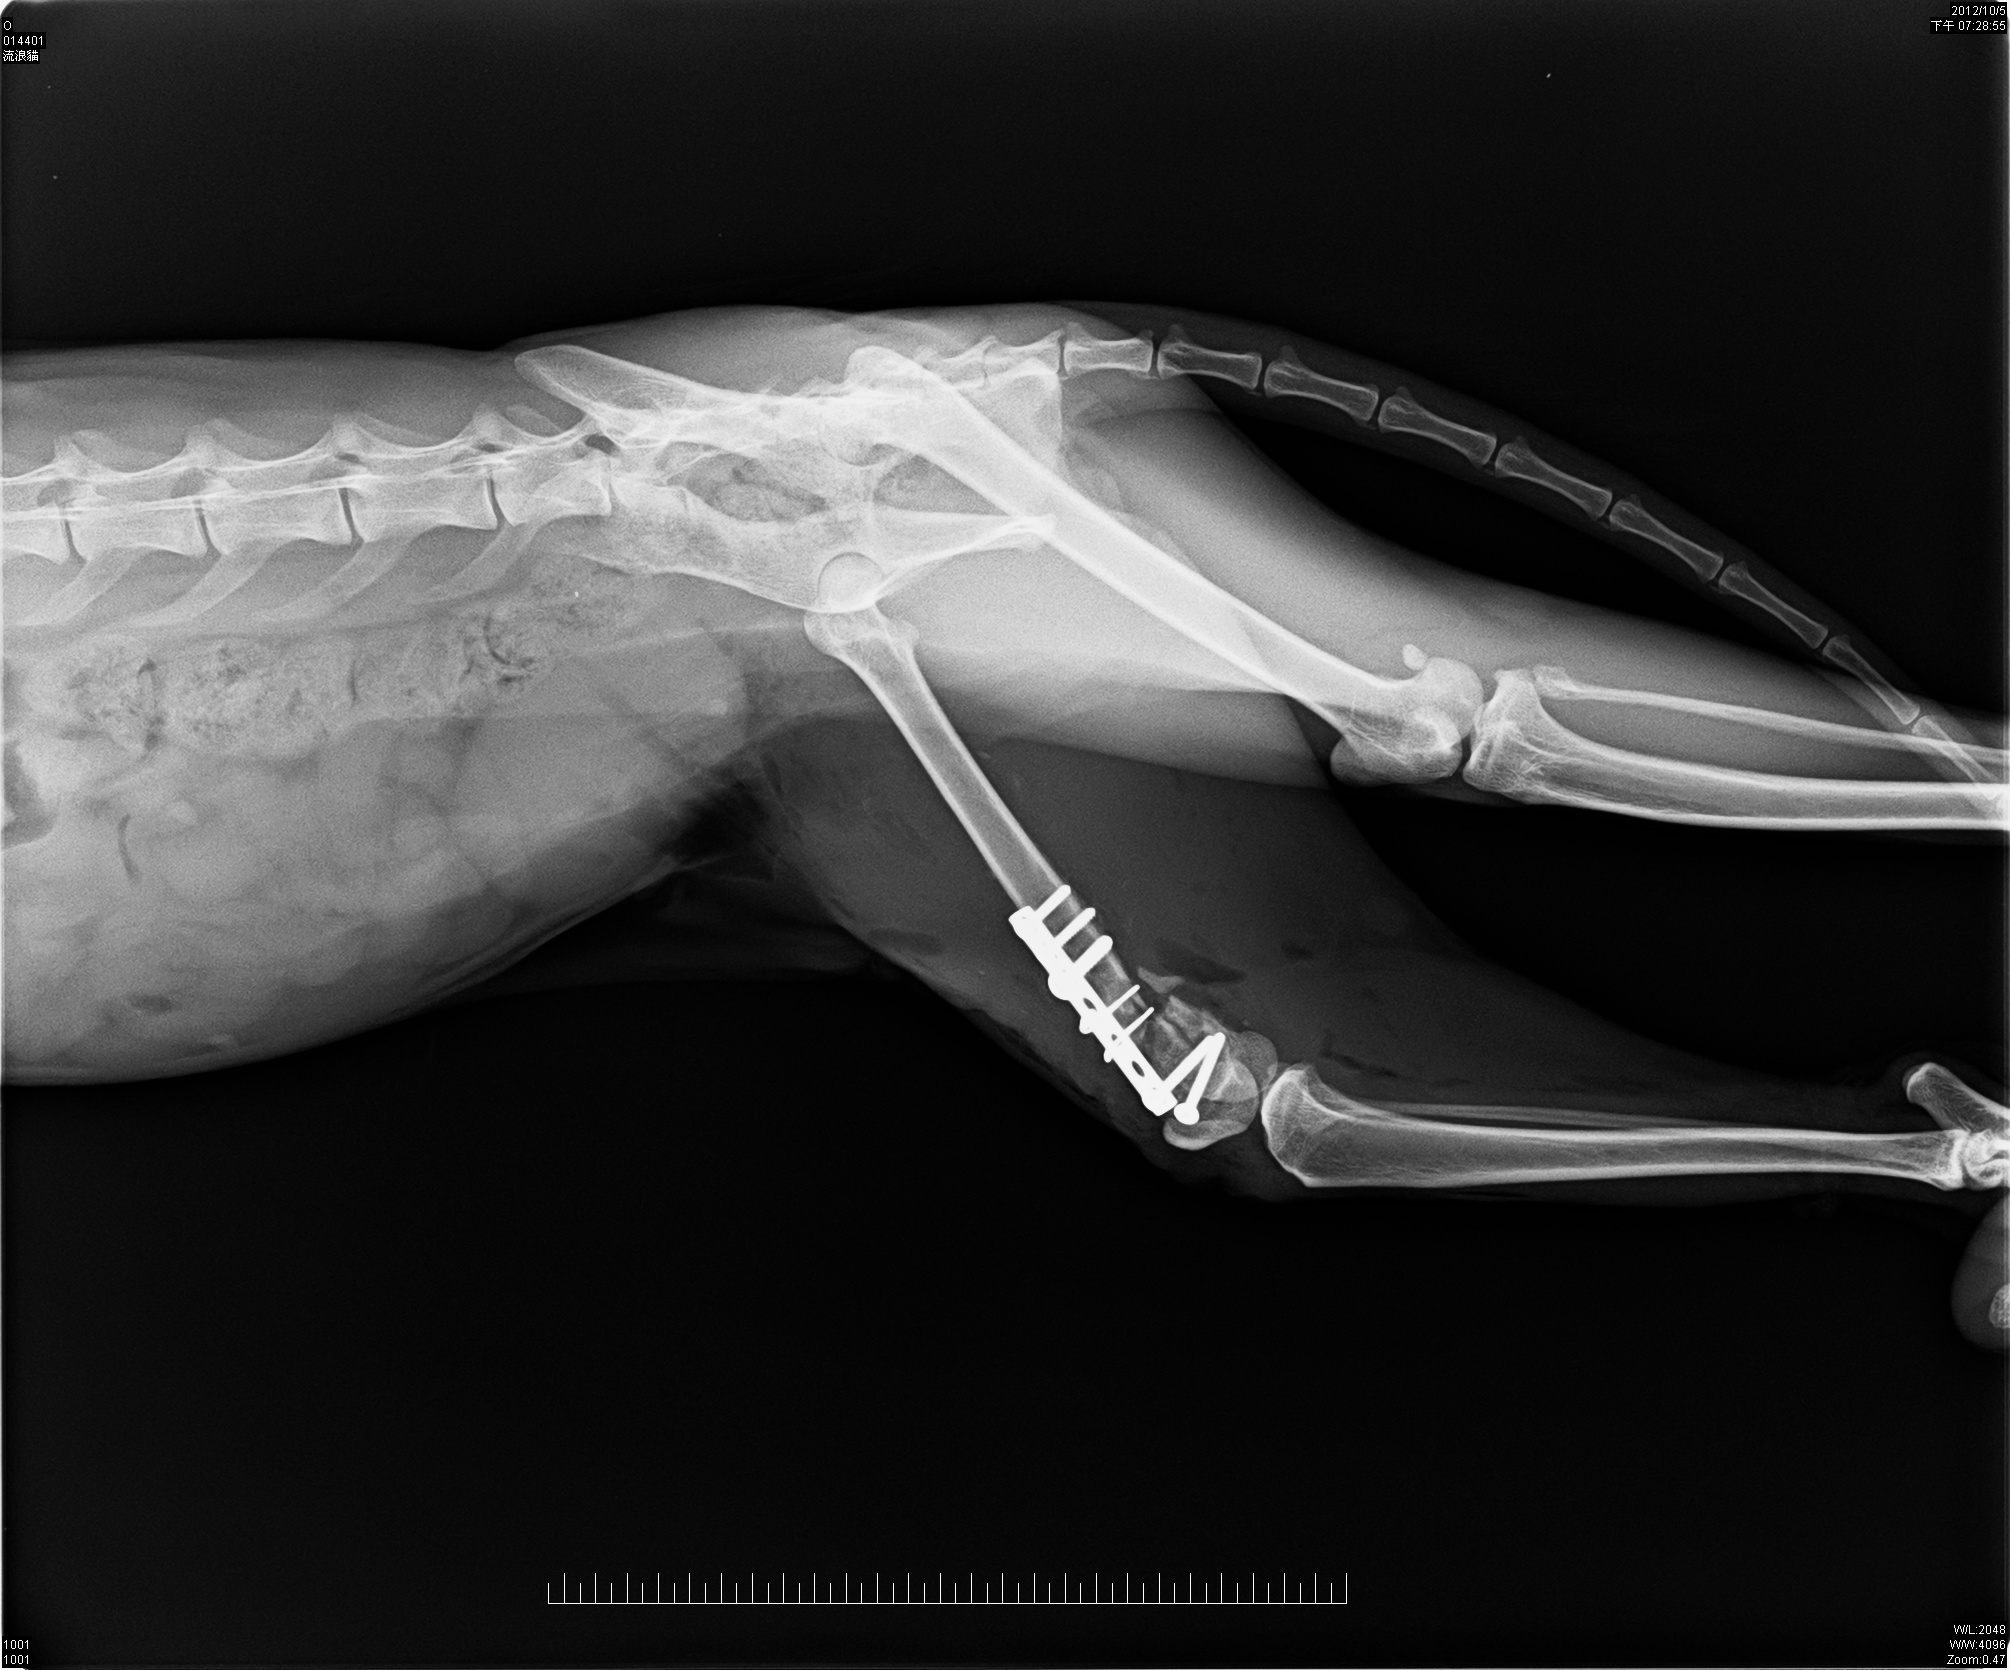

在醫院拍了X光片才得知虎斑妹妹的腳斷了,骨頭有粉碎需要開刀並打上鋼釘;但因為虎斑妹妹太瘦弱,所以先做結紮手術後,在醫院休養了幾天再安排手術!!!

10/05住院點滴止痛......................800*1天(原收費1500/天)

10/05左股骨遠端骨折手術.......10000*1次(原收費15000)

10/6~10/12住院點滴治療..............500*7天(原收費1000/天)

10/13~11/15住院治療....................300*34天(原收費500/天)

X-ray 4張.....................................優待不計(原收費400/張)

總計:800+10000+3500+10200=24500